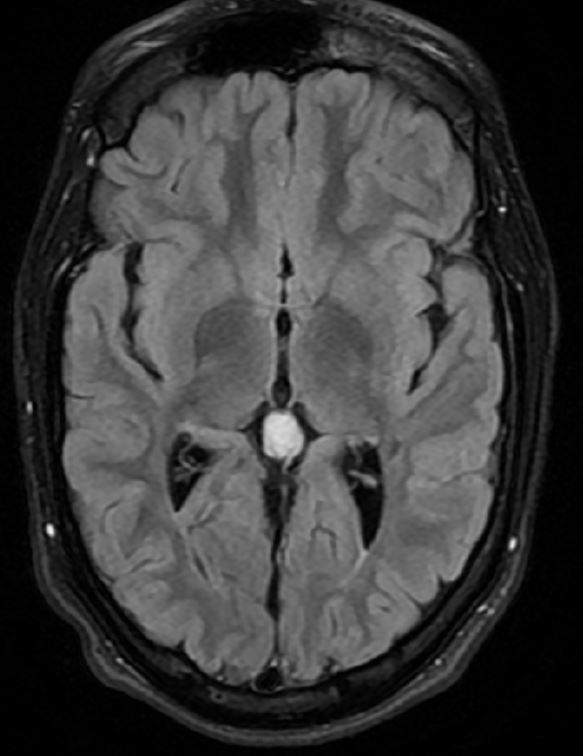

The MRI was reported as normal, but I think it shows thinning of white matter posteriorly, but no clear ulegyria: